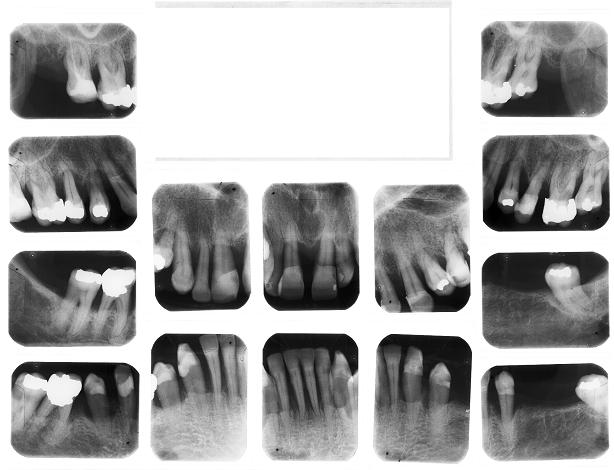

O paciente com doença periodontal deve seguir um controle de escovação adequado, como mostra o quadro a seguir.